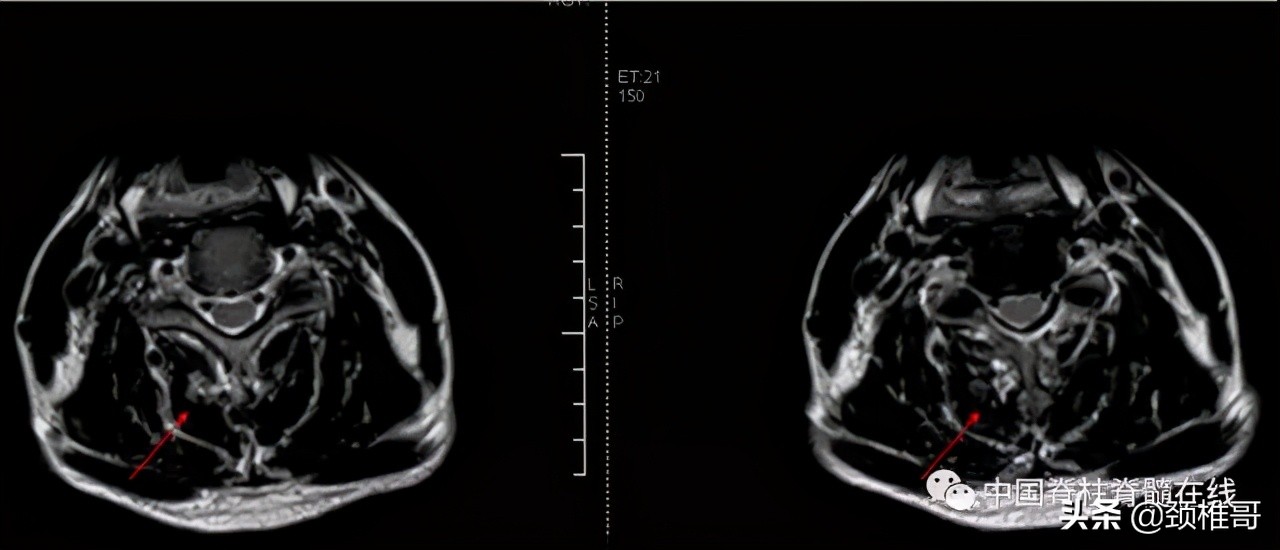

另外一个例子,这是一个头晕8年的病人,他的颈椎核磁共振显示,颈椎3-6各个节段之间的椎间盘退变膨出,局部有一些骨质增生,但没有明显的神经受压,横断面扫描显示颈椎周围肌肉有严重的退变表现;在X线检查时发现,棘突排列顺序不佳,颈4/5椎体之间有台阶,颈椎3-7各个节段之间夹角增大,都超过了11度;过屈位显示颈2-4椎出现了双边征,是旋转不稳的表现。这个病人的椎间盘虽然已经出现了退变、膨出,并发生了骨质增生,对硬膜囊产生了轻度压迫。但是其主要问题是椎间盘退变吗?不对,其主要问题还是多节段的椎间不稳,既有夹角增大,又有台阶,还有旋转。导致此病人头晕的主要原因还是肌肉和韧带的控制能力的下降所导致的。

正位显示椎体序列不佳、侧位显示颈椎4/5之间台阶状改变

过伸过屈侧位X线片显示多节段颈椎不稳

在椎间盘膨出、颈椎不稳基础上发生的代偿性增生